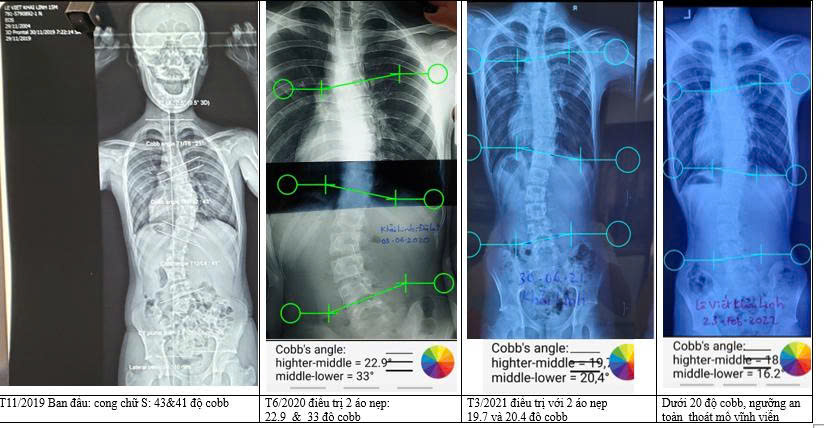

Lê Viết Khải Linh đến từ Đà Lạt – Lâm Đồng; 16 tuổi

Phát hiện cong vẹo cột sống đường cong đôi chữ S: trên 43 độ, dưới 41 độ cobb.

cột sống cong vẹo của khải Linh trước khi điều trị bằng phương pháp áo nẹp chỉnh hình

Đây là ngưỡng chỉ định mổ. Khải Linh cũng đã làm thủ tục hồ sơ đầy đủ. Tuy nhiên vào phòng mổ, phút chót, mẹ con em đã quay đầu, đổi ý.

Ngay khi nhận áo nẹp, Khải Linh rất tuân thủ quy trình mặc áo. Với sự cố gắng và quyết tâm con đã hoàn thành xuất sắc.

Con một chàng trai giàu ý chí, nghị lực và quyết tâm cao. Con đã nỗ lực và kiên trì, sau gần 3 năm điều trị bằng phương pháp mặc 2 áo nẹp ngày và đêm. Chạy đua nước rút, bước chân vào đại học cũng là lúc xương con cốt hóa định hình xong.

Con đã làm được, thoát mổ vĩnh viễn, cú lội ngược dòng siêu đỉnh.